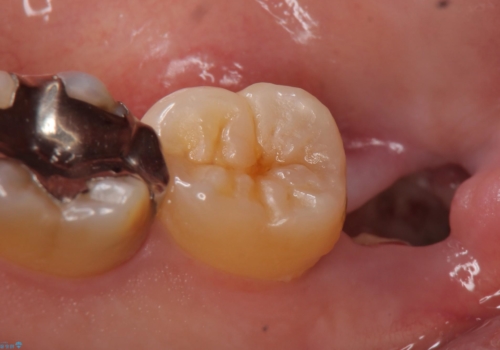

- 右下奥歯がたまにしみるので診て欲しいといらっしゃった方の症例です。

右下7番目の歯の歯茎より深い位置に虫歯があったため、親知らずを抜歯後PGA(ゴールド)インレーによる修復を行いました。